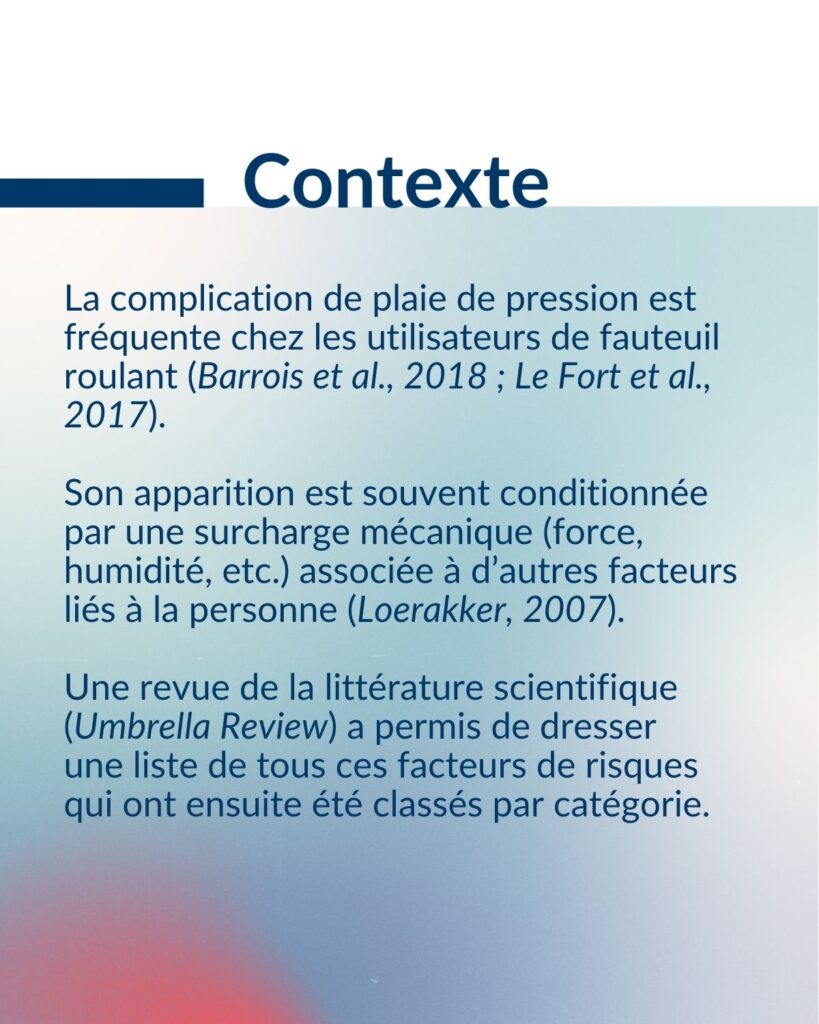

Les multiples facteurs de risque derrière les plaies de pression

Une synthèse de la littérature existante a permis d’identifier les multiples facteurs personnels associés à l’apparition des plaies de pression et de mesurer leur importance.